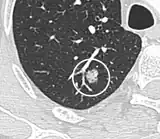

-

Low attenuating nodule (in this case a fat containing hamartoma).[9] -

Cavitation with relatively thick wall, in this case aspergilloma).[9]